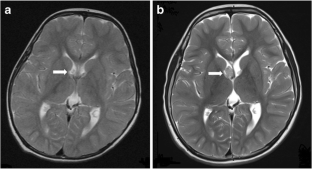

Fig. 1

Fig. 2